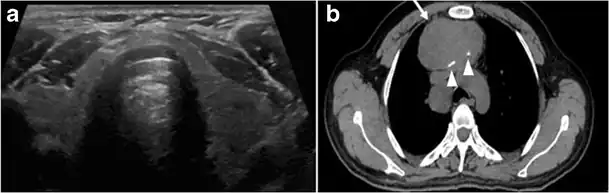

Fig. 14. A 19-year-old male patient known to have multi-nodular goiter and FNA, showing underlying Hashimoto's thyroiditis. a, b Sagittal and transverse greyscale and colour Doppler ultrasound of the neck demonstrate a hypoechoic enlarged right thyroid lobe with small hyperechoic regenerative nodules and marked hypervascularity (white arrows). c, d Enhanced axial CT scan images of the neck demonstrate a heterogeneously enhancing and enlarged thyroid gland, left more than right lobe, and the trachea is markedly narrowed.[1] -